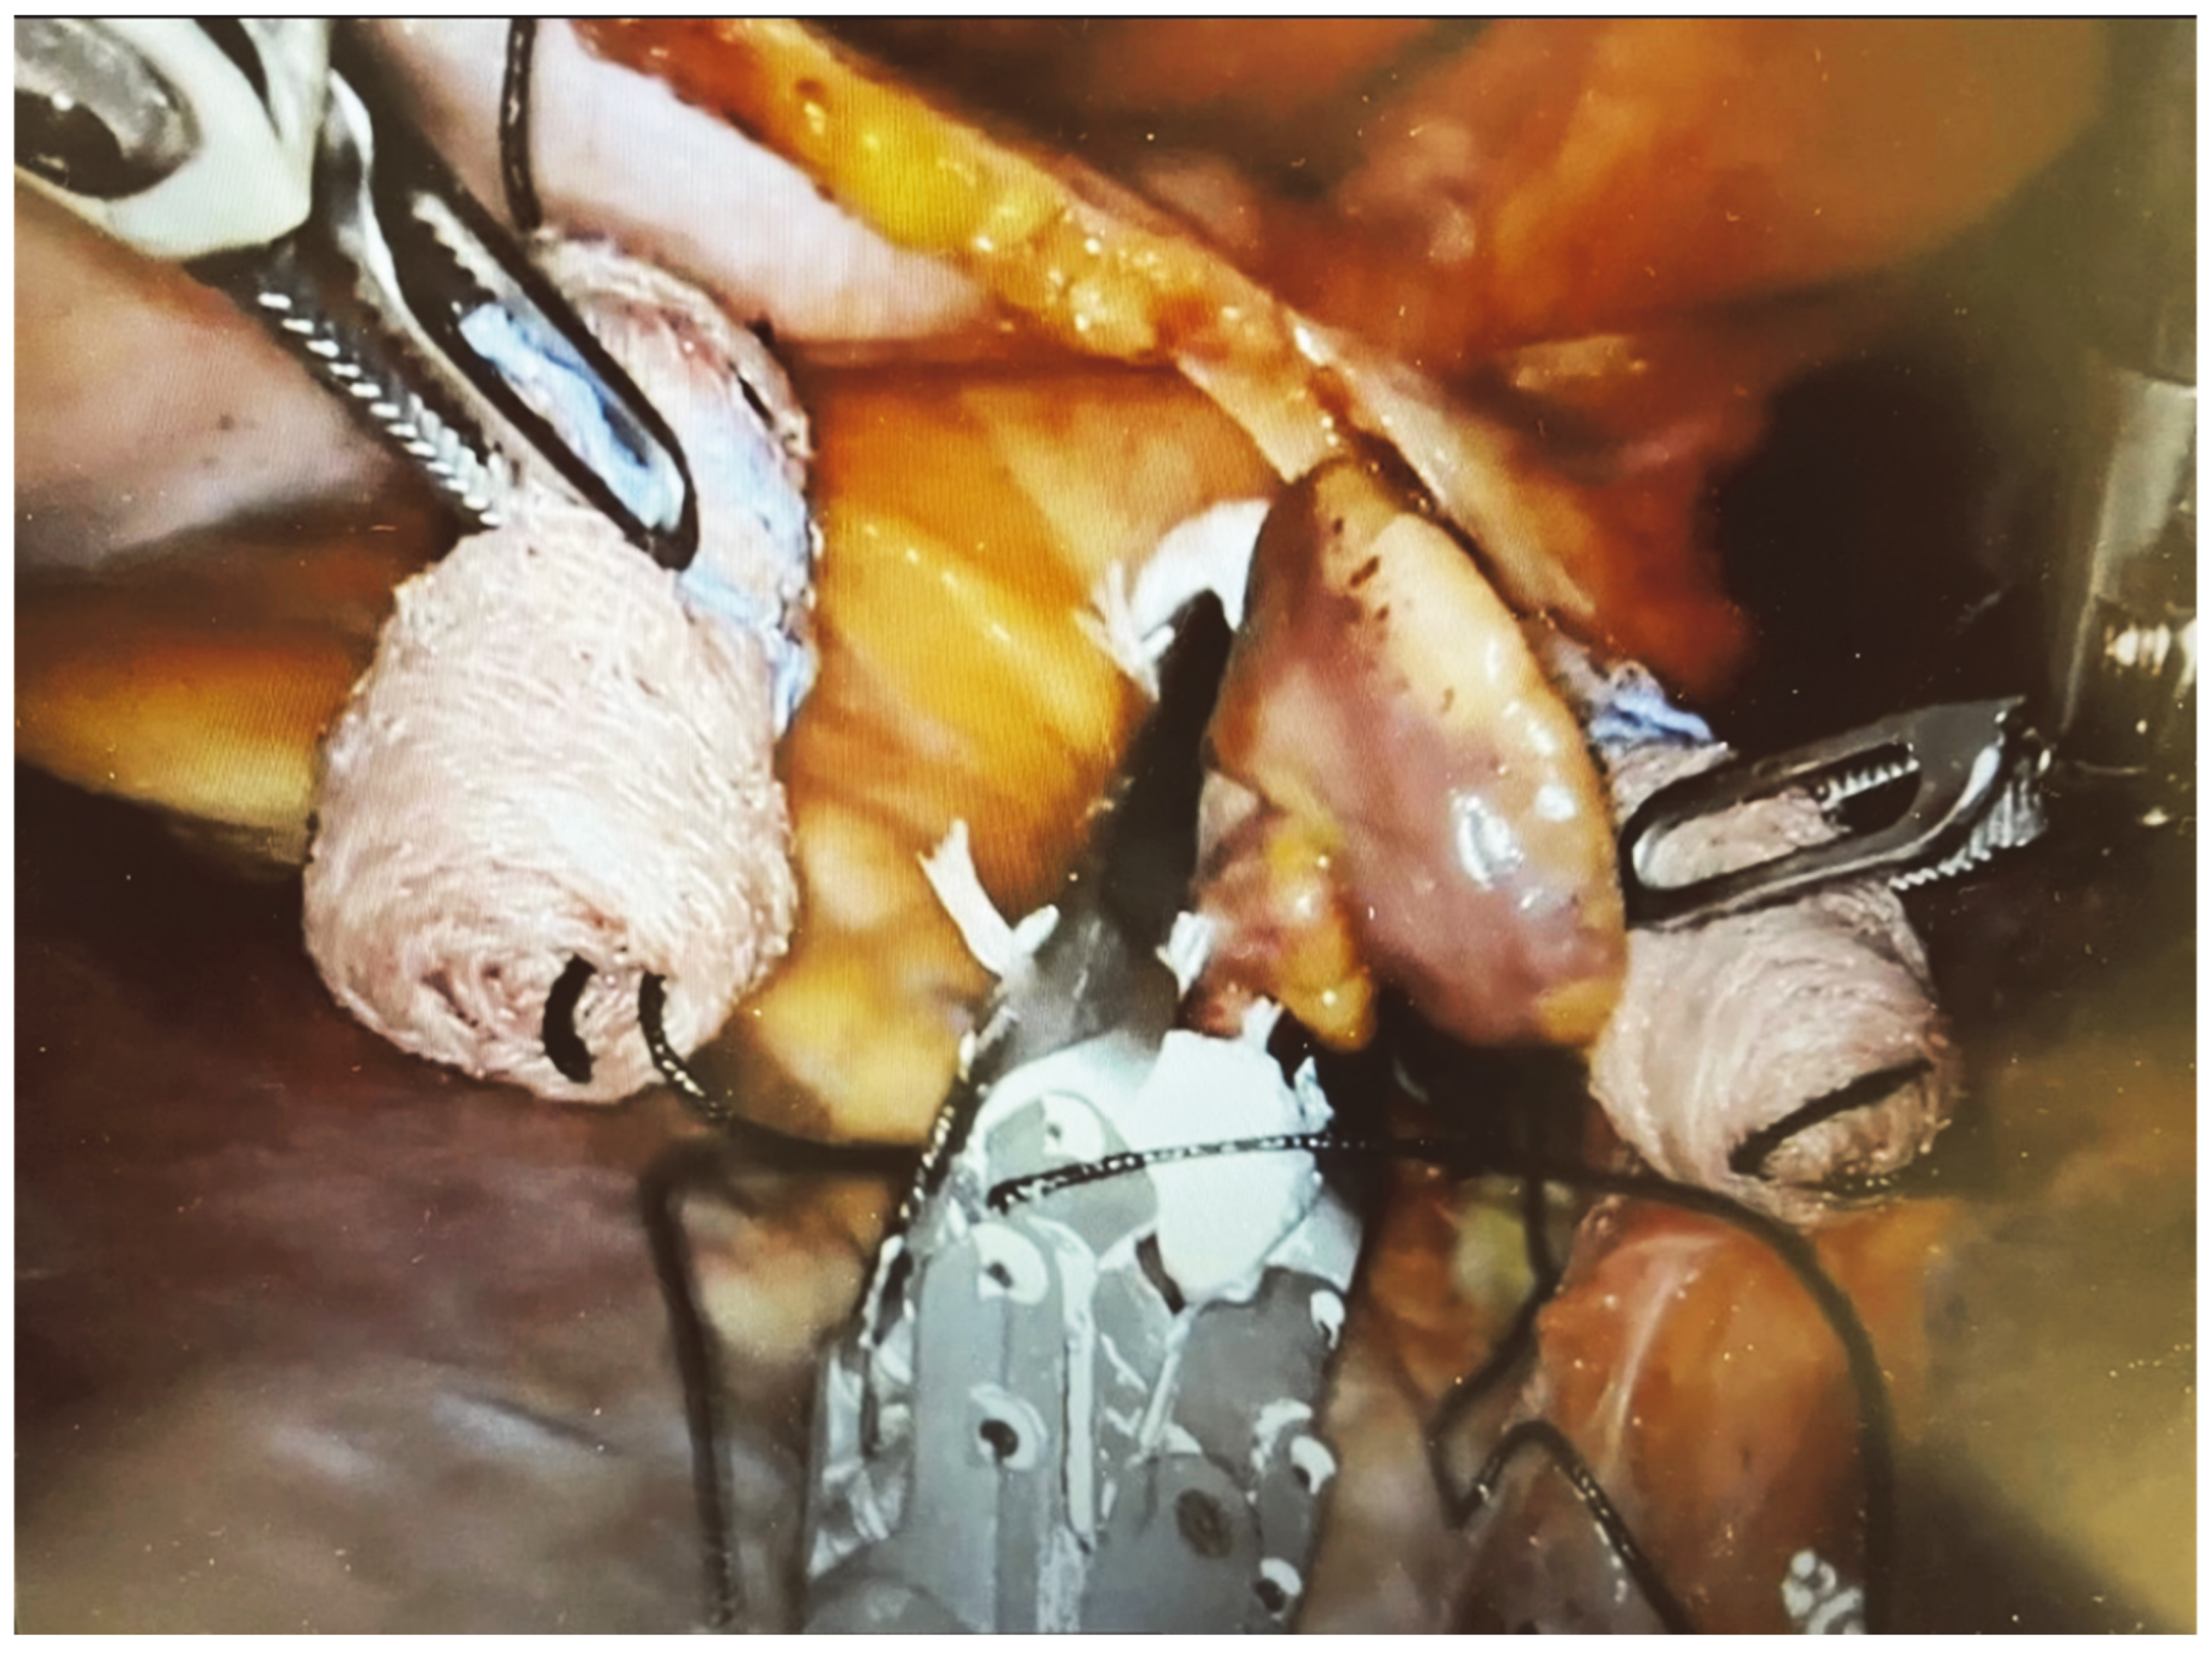

2.3. Surgical Technique